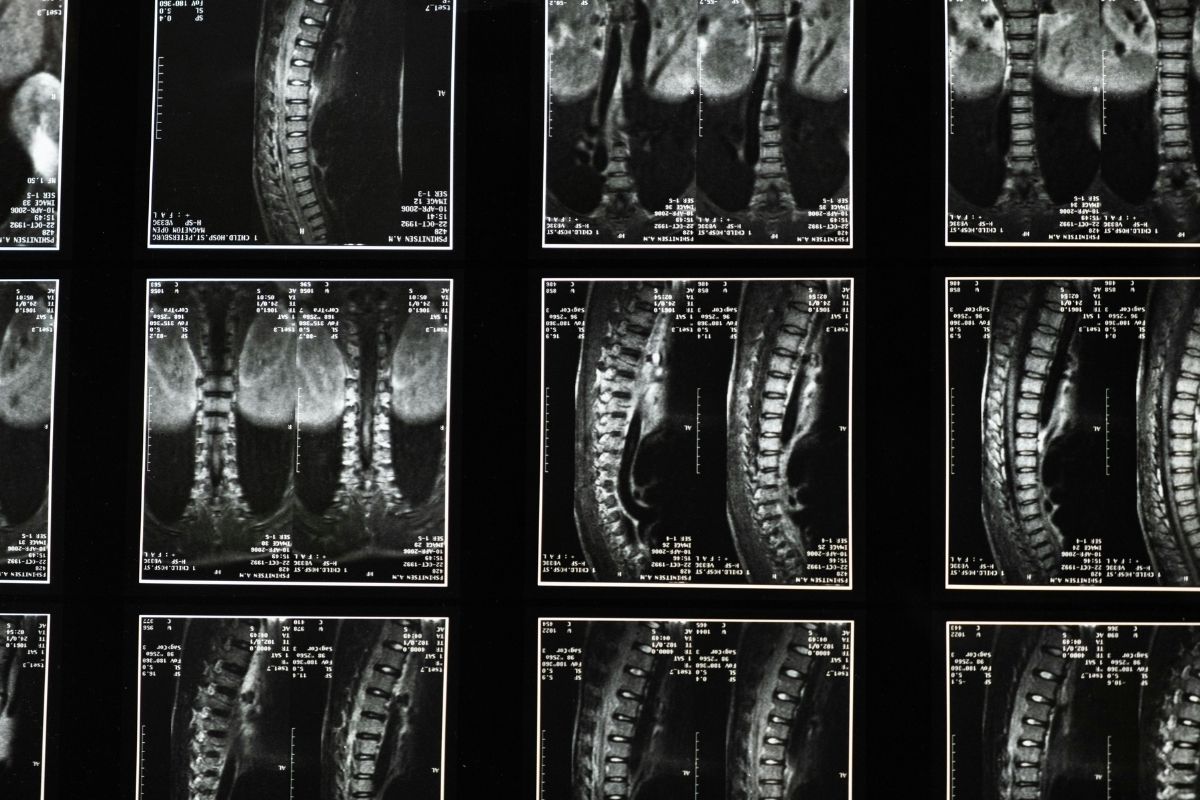

Investigadors de la Universitat Pompeu Fabra (UPF), en col·laboració amb l’Hospital del Mar, han desenvolupat models computacionals que permeten simular cirurgies de columna vertebral personalitzades a cada pacient. La tecnologia facilita la detecció i la prevenció de riscos abans de l’operació, amb l’objectiu que la intervenció es pugui fer de manera més segura. En concret, els models virtuals corregeixen la deformitat de la columna en adults –ASD, en anglès–, una patologia que altera l’alineació vertebral i l’equilibri postural del pacient i que provoca dolor i limitació funcional.

Per corregir la deformitat cal fer complexos muntatges, anomenats instrumentacions, que consisteixen a col·locar cargols dintre de les vèrtebres connectats per barres. Tot i els avenços mèdics, les intervencions comporten riscos importants de complicacions mecàniques, com la fallada de la unió proximal, com es diu l’afectació de la unió entre l’última vèrtebra instrumentada i la primera vèrtebra mòbil. Això pot causar diferents lesions, des de fractures fins a la compressió de la medul·la espinal, amb conseqüències greus com dolor invalidant, incapacitat per mantenir-se dret o problemes de mobilitat a les cames. La seva afectació és del 30% dels pacients i la solució requereix una cirurgia.

Per afrontar el repte i reduir el risc de segona cirurgia, un equip de la Unitat de Recerca BCN MedTech del Departament d’Enginyeria de la UPF, en col·laboració amb l’Hospital del Mar, ha desenvolupat models computacionals sofisticats i específics per a cada pacient. Els models permeten recrear, de manera virtual, diferents escenaris quirúrgics i forces biomecàniques, i ofereixen dades quantitatives que complemen les avaluacions clíniques existents. L’hospital ha proporcionat la hipòtesi clínica i els casos clínics reals per validar simulacions i així els investigadors poden centrar-se en els pacients més complexos i de més risc, cosa que permet ajustar l’estratègia quirúrgica a les característiques de cada cas abans d’entrar a quiròfan.

L’estudi mostra que una estratègia quirúrgica anomenada reducció de la densitat d’implants –IDR, en anglès– pot reduir de manera significativa les complicacions postoperatòries. L’IDR consisteix a utilitzar menys cargols de manera estratègica per fixar la columna, i així disminuir la tensió entre els discos i millorar l’estabilitat dels implants. En pacients amb ossos sans i implants de titani, el treball apunta que la tècnica pot reduir fins a un 70% la tensió sobre els discos i millorar més d’un 140% l’estabilitat de cargols restants. La distribució planificada i estratègica permet a la columna suportar millor les tensions naturals després de la cirurgia i reduir el risc de complicacions.